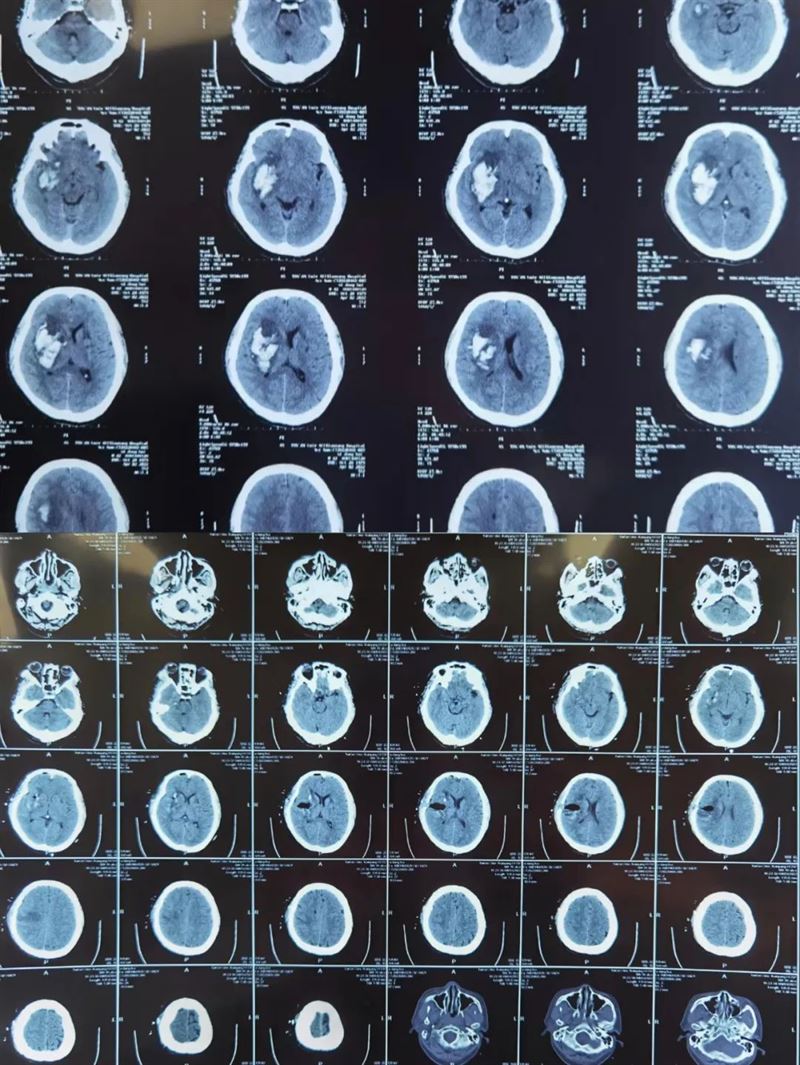

之前,我院急診科緊急接來了一名陷入深昏迷狀態(tài)的男性病人,患者入院后急查頭顱CT提示顱內(nèi)出血,量約90ml。亓乾偉副主任醫(yī)師接治病人后,發(fā)現(xiàn)患者雙側(cè)瞳孔不等大,一側(cè)瞳孔已經(jīng)散大,病情危急,充分告知患者家屬當(dāng)前病情及預(yù)后情況,顱內(nèi)出血量大,發(fā)病時間短,隨時存在呼吸心跳驟??赡埽<吧?,建議緊急手術(shù)治療,與其妻子及遠(yuǎn)在北京的女兒電話聯(lián)系并取得家屬同意后,在入院1小時內(nèi)緊急行開顱手術(shù),術(shù)中清除血腫并仔細(xì)止血后,在其腦表面發(fā)現(xiàn)腫瘤病灶,一并切除病灶并送病理檢查。術(shù)后患者生命體征平穩(wěn),復(fù)查頭顱CT可見血腫清除滿意,將患者從死神手中拉回。術(shù)后病理結(jié)果提示肝細(xì)胞轉(zhuǎn)移瘤,并予以相應(yīng)治療?;颊咂拮蛹芭畠豪氖终f到:“要不是您,我都沒有機(jī)會再見我父親最后一面,將會徹底失去我盡孝的機(jī)會?!?br />

此類事跡數(shù)不勝舉,就在5個月前的一個凌晨,神經(jīng)外科一病區(qū)接診了一名男性腦外傷患者,據(jù)陪同來的房東所述,患者是藏族人,21歲,孤身一人來到咸陽,其余信息都無從所知,當(dāng)時患者病情十分危急,意識呈昏迷狀態(tài),瞳孔散大,去腦強(qiáng)直,呼吸微弱,如不進(jìn)行緊急搶救,年輕的生命將離我們而去。科室劉增強(qiáng)主任立即啟動急救綠色通道,亓乾偉醫(yī)生徹夜未眠,歷經(jīng)5個多小時的艱苦奮戰(zhàn),手術(shù)順利完成,但患者仍然未脫離危險,呼吸機(jī)維持呼吸,在亓乾偉醫(yī)生的精心治療下,終于在術(shù)后1周患者自主呼吸恢復(fù),術(shù)后1月患者意識恢復(fù),術(shù)后2月患者已完全康復(fù),下地活動自如,順利出院?;颊吒改敢圆刈逄赜械姆绞綖樨燎瑐メt(yī)師獻(xiàn)上了潔白的哈達(dá),送上了藏族特有的祝?!霸鞯吕铡薄?

(術(shù)前術(shù)后對比)